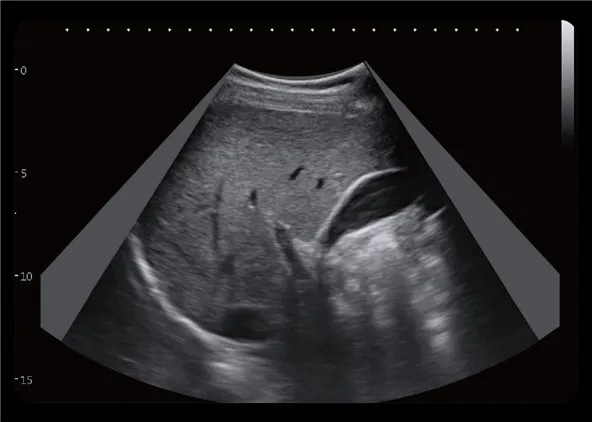

Expansión curva

Amplíe el área de escaneo en la sonda convexa, igual que el trapezoide convexo.

Mejor para la exhibición de órganos grandes, especialmente hígado, riñón a través del espacio de las costillas.